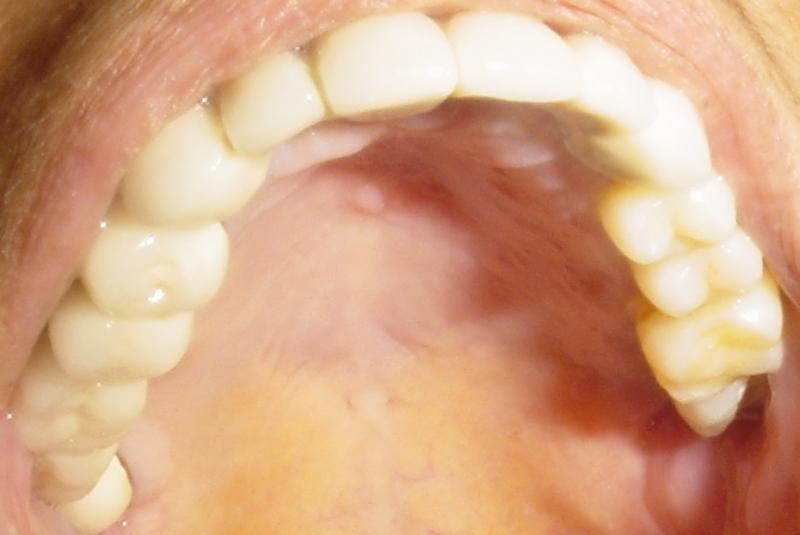

PICTURES OF PATIENTS

BEFORE AND AFTER RESULTS

BEFORE

AFTER

HOLLYWOOD SMILES

patient aged 52 with yellow , broken, uneven & missing teeth asked for permanent solution.

Before ore

ore

Patient aged 31 years walked in and asked for filling gaps in teeth ,replacing missing tooth & permanent teeth whitening.

BEFORE

AFTER

********************************************************** PATIENT AGED 28 YEARS WITH IRREGULAR TEETH DONE HOLLYWOOD SMILE DESIGNING AND PERMANENT WHITENING

PATIENT AGED 52 YEARS CHIEF COMPLAINT IRREGULAR ,YELLOW TEETH

DONE HOLLYWOOD SMILE DESIGNING AND PERMANENT TEETH WHITENING

BEFORE

AFTER